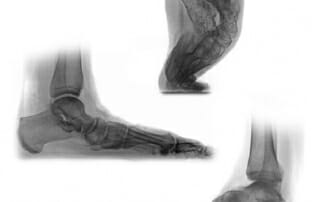

Dr. Kinast: Worauf ist bei einem Hohlfuß zu achten?

Was muss bedacht werden, wenn ein Patient einen Hohlfuß (Subtle cavus foot) aufweist? Auch bereits bei einem kleinen Ansatz für einen Hohlfuß muss mit Spätfolgen gerechnet werden. Bettende Einlagen können [...]